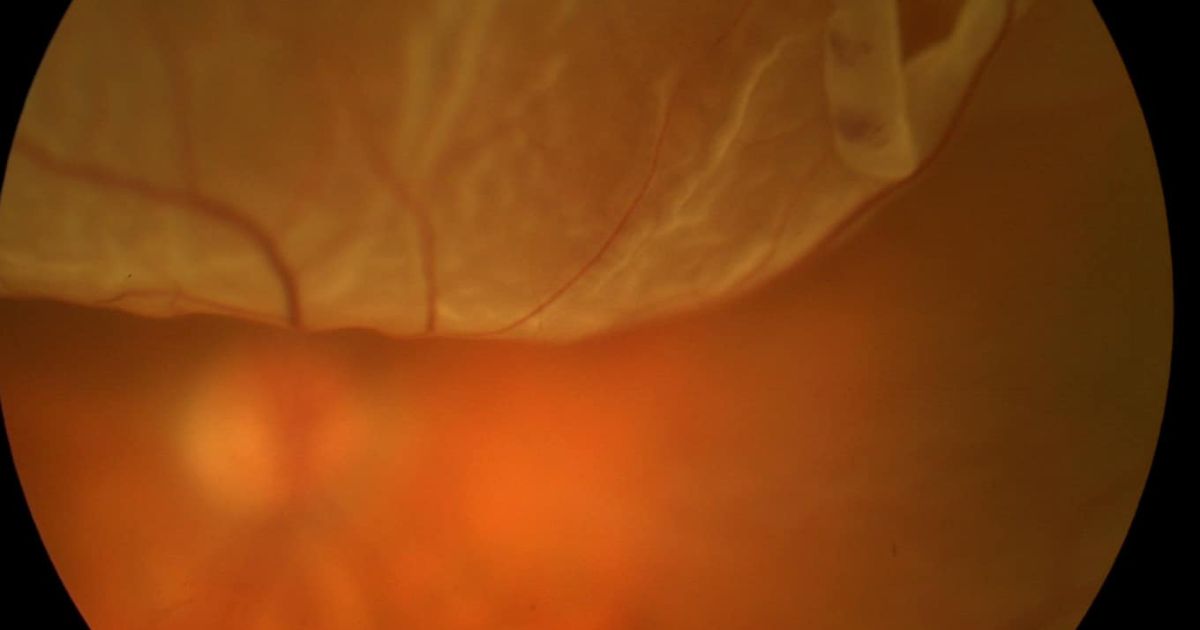

Đối với các ca bệnh bong võng mạc:

Khi đã xảy ra bong võng mạc, người bệnh bắt buộc phải điều trị bong võng mạc trước, thường bằng các phương pháp phẫu thuật như độn đai củng mạc, cắt dịch kính hoặc các kỹ thuật đặc thù khác tùy mức độ tổn thương.

Trong giai đoạn này, không nên mổ cận thị ngay vì mắt cần thời gian hồi phục hoàn toàn. Việc tiếp tục phẫu thuật cận khi võng mạc chưa ổn định có thể làm tăng nguy cơ kích ứng, biến chứng và ảnh hưởng xấu đến thị lực.